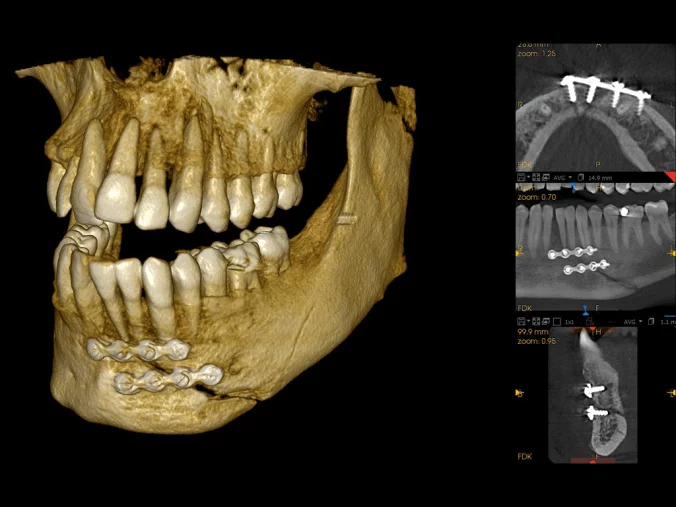

Multifunkční systém

Multifunkční zobrazovací systém v jediné výkonné jednotce obsahuje 2D panoramatické zobrazení a 3D CBCT zobrazení včetně možnosti skenování modelů a 3D faciálního skenování. Lze jej dále rozšířit o cephalometrický modul.